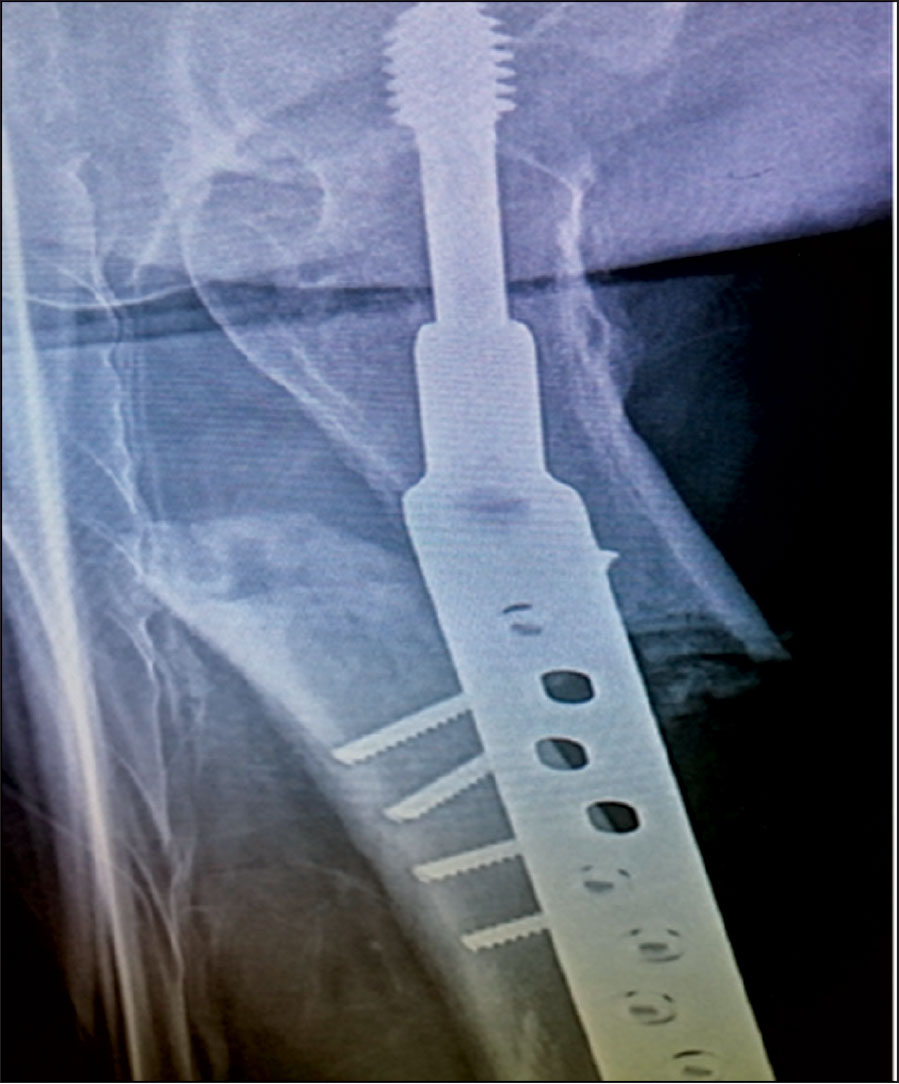

An 83-year-old woman presented to hospital with low energy trauma resulting in non-weight bearing and pain in her right thigh. She had chronic obstructive pulmonary disease (COPD), diabetes mellitus type 2, gastroesophageal reflux disease (GERD) and osteoporosis. She had a right neck of femur intertrochanteric fracture in 2010 for which she had a two-hole dynamic hip screw (DHS) plate.

She was started on alendronate therapy in 2011 for osteoporosis. She had left distal radius fracture in 2013 for which she had manipulation under anaesthesia and k-wiring. She had a low energy trauma in January 2015 and was brought in with right thigh pain and non-weight bearing.

She had an x-ray right femur and pelvis showing an atypical right femur sub-trochanteric fracture. She was taken to the theatre the next day and her two-hole plate was removed without taking the lag screw and was replaced with an eight-hole DHS plate. She was started on physiotherapy and within a few weeks she was walking with a walking frame. She was followed up with regular x-ray. Her alendronate was stopped and she started on teriparatide injections. Teriparatide is a man-made form of the hormone parathyroid which exists naturally in the body.

Figure 1. DHS two-hold plate for neck of femur fracture(click to enlarge)